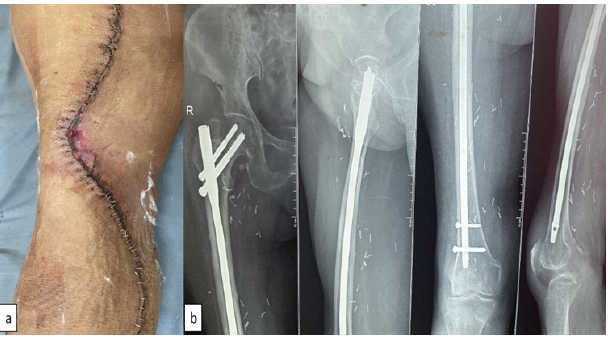

Full weight-bearing walking with walker and knee range of motion exercise was allowed as tolerated. There was small marginal skin necrosis which healed with dressing (Fig. 3). Final histopathology report came out to be liposarcoma with foci of low-grade dedifferentiation (FNCLCC Grade 3) [8] and dimension of tumor was 29 × 24 × 11 cm.

Figure 3: Post-operative image of the wound and radiograph; (a) post-operative image showing superficial skin necrosis managed conservatively and (b) radiograph showing prophylactic nailing at a second stage to prevent radiotherapy-induced fracture.

Prophylactic nailing was done at a second stage after primary wound healed to prevent radiotherapy related fracture [5,6] (Fig. 3). Patient received adjuvant radiotherapy 60 gray in 30 fractions [9] without any complication. Patient was offered chemotherapy [10] but patient refused.